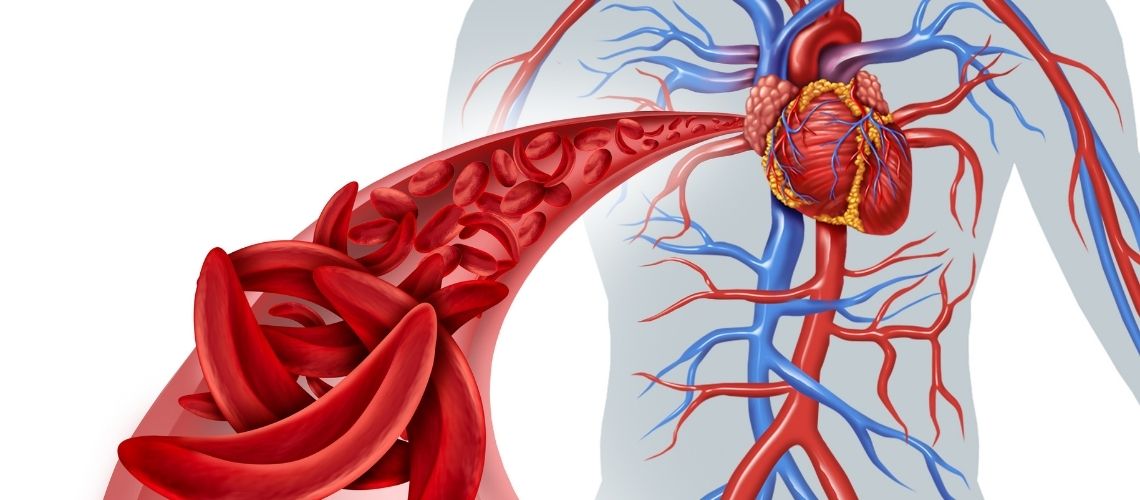

Koroner Anjiyografi, kalp damarlarını görüntülemek için kasıktan veya el bileğinden arterlere girilerek yapılan bir görüntüleme işlemidir. Bu işlem dahilinde, hastaya lokal anestezi veriliyor olduğundan, uyanma süreci söz konusu olmayacaktır. Hasta işlem sonrasında bilinci açık olacaktır. Anjiyo kateterinin giriş yaptığı doku üzerinde ise küçük bir açıklık söz konusu olduğundan, bunun zaman içerisinde herhangi bir yara gibi iyileşme durumu söz konusu olabilir. El bileğinden yapılan anjiyo işleminde hasta hemen gündelik yaşantısına dönebilirken, kasıktan yapılan anjiyo sonrasında hastanın 6 saat kadar kum torbaları veya özel kasık damarı kapatma cihazları ile sabitlenerek, yatar pozisyonda beklemesi gerekir.

Damar üzerindeki kesinin iyileşmesi için bu süre gereklidir. Aksi halde kanama meydana gelebilir ki, arterdeki kanama durumları riskli durumlar olduğundan, hastanın hareket etmesine izin verilmez. Her iki tür anjiyo durumunda da kateter girişi için açılan kesinin korunması çok önemlidir. Özellikle kasıktan yapılan anjiyo işlemlerinden sonra, hastanın ıkınma, hapşırma gibi eylemler burada kanamaya neden olabilir.

Anjiyografi sonrası en yaygın komplikasyon; girişim yapılan bölgede yanma, morarma ve şişmedir. Normal koşullarda belli ölçüde morarma ve ağrı beklenen durumlar olmakla birlikte, aşırı ve geçmeyen durumlarda hekime başvuru gereklidir. Girişim bölgesinde kanama, hastanın talimatlara uymaması veya sair sebeplerle meydana gelebilir. Bu durumda olabildiğince hızlı şekilde sağlık kuruluşuna başvurmak gereklidir. Yaygın olmamakla birlikte görülebilecek bir başka komplikasyon göğüs ağrısı ile birlikte seyreden kalp sorunları olabilir. Göğüste başlayıp sol kol, çene ve omuza uzanan bir ağrı durumunda vakit kaybetmeden hekime başvurmak gereklidir.